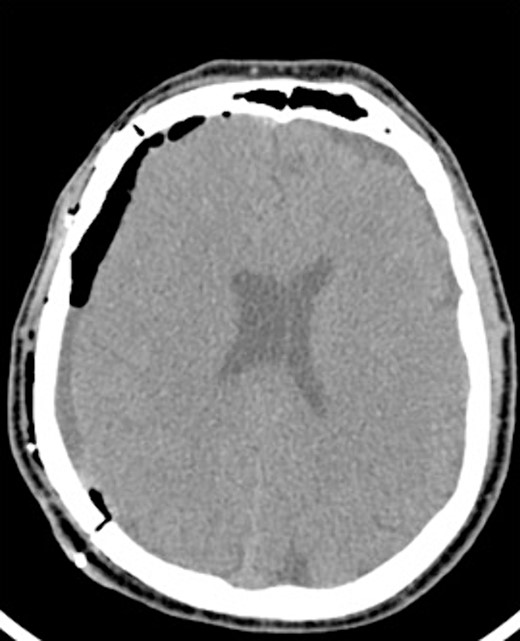

An 81-year-old male with a history of acute subdural hematoma, previously managed non-surgically, presented with worsened confusion and cognitive dysfunction. Repeat CT demonstrated expansion of right-sided subdural collection, consistent with cSDH (Fig. 4).

After the head was positioned in a supine neutral position on a horseshoe head holder, the AR system was used to overlay the hematoma and other relevant anatomy onto the patient’s head. Midline locations, vasculature and the blood collection were appreciated via AR overlay prior to marking an incision (Fig. 5). The AR overlay was then used to plan two separate linear incisions for two right-sided burr holes—one frontal and one parietal over the largest components of the hematoma as visualized with AR. A perforator drill was used to create the two burr holes which were widened with a burr and rongeurs. Beneath the dura, a hematoma was identified and its thick membrane layer was coagulated with bipolar cautery. The surgical sites were irrigated with saline to evacuate chronic blood. A ventriculostomy catheter was then placed into the subdural space at the frontal burr hole and tunneled lateral to the incisions. The burr holes were covered with titanium covers. There were no intraoperative complications, and the tolerated procedure well with improved cognitive function several days after surgery. Post-operative CT demonstrated significant interval decrease in hematoma volume and reduction in midline shift (Fig. 6).